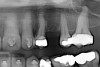

Figure 4a  Corticotomy SFOT. A 42-year-old male presented with a history of extraction orthodontic therapy (A). Incisors were too upright and had severe incisal wear. He was concerned about esthetics of the worn teeth and his insufficient lip support.

Figure 4b  Progress photo and panorex 9 months after corticotomies were performed on Nos. 6 through 11 (B and C). Previous extraction sites were reopened orthodontically to improve function and fill lip support. Incisal edges were restored provisionally with composite resin. Note that despite the creation of adequate spaces to replace missing teeth, there is inadequate room for placement of dental implants because of severe tipping of all the anterior teeth. Osteotomy SFOT may have been a better choice because it would have allowed needed alveoloskeletal correction (without excessive tipping) instead of the primarily dentoalveolar correction common in corticotomy SFOT. Restorative dentist: Brad Jones, DDS.

Figure 4b

Figure 4c  Progress photo and panorex 9 months after corticotomies were performed on Nos. 6 through 11 (B and C). Previous extraction sites were reopened orthodontically to improve function and fill lip support. Incisal edges were restored provisionally with composite resin. Note that despite the creation of adequate spaces to replace missing teeth, there is inadequate room for placement of dental implants because of severe tipping of all the anterior teeth. Osteotomy SFOT may have been a better choice because it would have allowed needed alveoloskeletal correction (without excessive tipping) instead of the primarily dentoalveolar correction common in corticotomy SFOT. Restorative dentist: Brad Jones, DDS.

Figure 4c